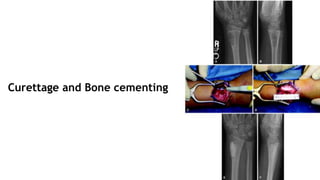

● Curettage is not sufficient, as tumor may recur.

● En Bloc excision and filling cavity with

autogenous bone results in high rate of cure.

● Despite Wide excision , if tumor recurs then

additional studies should be done to rule out

malignant transformation.

Curettage and Bone cementing